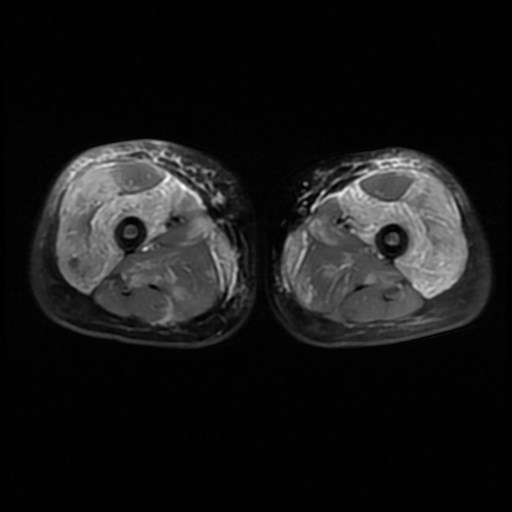

3. Muscle magnetic resonance imaging:

Magnetic resonance imaging (MRI) is a diagnostic imaging test that allows indirect assessment of the presence of muscle inflammation. It is performed with the patient lying down, requiring that the child does not move during the time in which the images are taken. It does not radiate, does not require the administration of contrast, but the usual duration is 30-45 minutes so that, in cases of younger age may be necessary sedation of the patient. It can be performed on a specific area of the body or the whole body, allowing us to assess the extent of the inflammation. The MRI has allowed us to verify the involvement of muscles that were initially thought to be respected, such as the distal muscles of the extremities (further away from the trunk). We can therefore affirm that JDM is a predominantly but not exclusively proximal myopathy.

It allows us to assess muscle, fascia and subcutaneous cellular tissue and to detect inflammation in clinically unaffected muscles. It is an objective test that allows differentiation of activity from muscle damage and that normalizes with treatment, making it a useful tool in patient follow-up. It also has prognostic value, as a relationship has been described between the involvement of the subcutaneous cellular tissue and the development of calcinosis.

The main problem is that at present there are no standardized sequence protocols or a single resonance assessment scale. Different research groups are working in this direction in order to homogenize clinical practice.